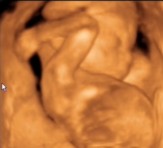

Csipet! Naaaaagy gratul a kis kukacoshoz

Maki nektek meg a tuti kiscsajhoz

De jók a képek!!